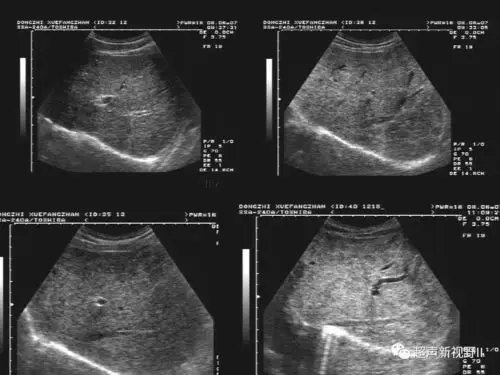

1. 腹部超声影像

超声微课堂腹部超声肝硬化

腹部超声检查常用切面